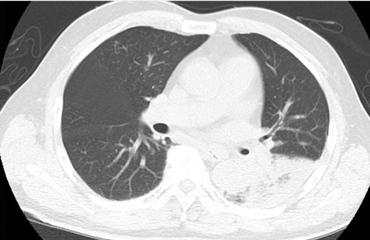

救急外来を紹介されるとCT撮影されます。

左下肺に限局した浸潤影とすりガラス陰影を認めます。

この所見を見たら尿中抗原を必ず確認してレジオネラを否定する必要があります。